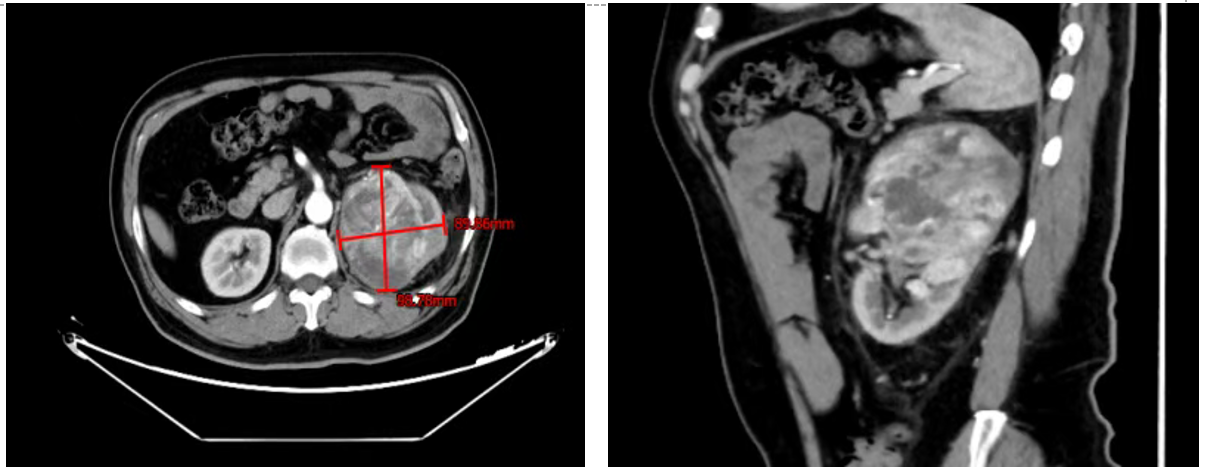

腹部CT:左肾占位性病变,考虑肾肿瘤可能性大,伴左肾静脉癌栓形成,左侧肾盂及输尿管上段受侵:腹膜后增大淋巴结病史。

2024年2月25日,给予培唑帕尼(800 mg,po,QD)治疗,持续半年。治疗1周后,患者血尿症状消失。

2024年3月13日,培唑帕尼治疗3周时,影像学检查提示原发灶肿瘤呈缩小趋势。

2024年4月26日,培唑帕尼治疗2个半月时,影像学检查提示原发灶肿瘤显著缩小。

2024年5月27日,培唑帕尼治疗3个半月时,影像学检查提示原发灶肿瘤进一步缩小,切除可能性提高。治疗过程中,患者一般状况良好,无严重不良事件发生,仅出现轻微恶心与呕吐(均为1级)。调整治疗方案,加用骨保护剂药物地舒单抗(120 mg,ih,Q4W)。